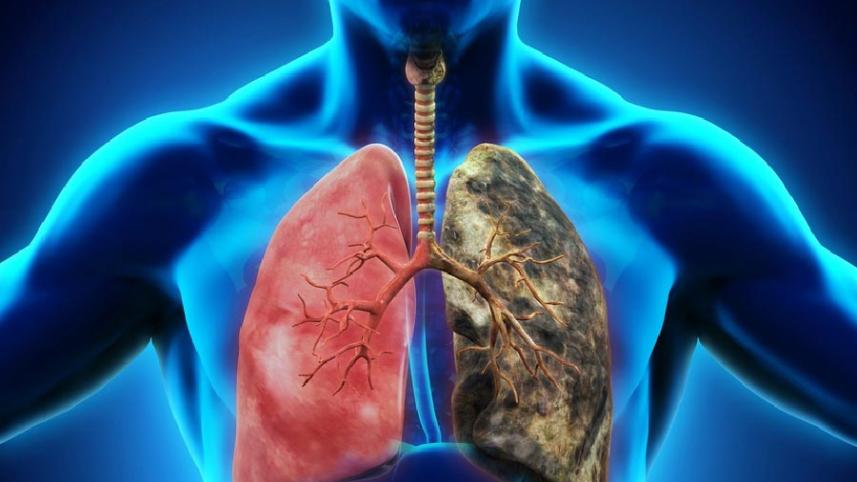

ডা. আব্দুস শাকুর খান বলেন, ফুসফুসের ক্যানসার হচ্ছে ফুসফুসের এক ধরনের টিউমার। অর্থাৎ ফুসফুসের যে স্বাভাবিক কোষ আছে সেই স্বাভাবিক কোষের যখন অস্বাভাবিক এবং অনিয়ন্ত্রিত বৃদ্ধি হয়ে চাকার মত সৃষ্টি করে, তাকেই ফুসফুস ক্যানসার বলে। এটি শরীরের জন্য মারাত্মক ক্ষতিকর। ক্যানসার যখন ফুসফুসে হয় এটা শুধু নির্দিষ্ট জায়গায় থাকে না বরং অস্বাভাবিক এবং অনিয়ন্ত্রিত বৃদ্ধির কারণে শরীরের অন্যান্য অংশেও ছড়িয়ে পড়ে। সঠিক সময়ে শনাক্ত ও যথাযথ চিকিৎসার অভাবে শেষ পর্যন্ত মৃত্যুরও কারণ হয়ে থাকে।

ফুসফুসের ক্যানসার হওয়ার সরাসরি কারণ বলা কঠিন। কিন্তু বিভিন্ন গবেষণায় দেখা গেছে, জীবনযাপনের ক্ষেত্রে কিছু ব্যতয় ঘটে যার কারণে ফুসফুসের ক্যানসার হতে পারে। কিছু ঝুঁকিপূর্ণ গোষ্ঠী আছে, যেমন- যারা ধূমপান করেন, তামাকজাত দ্রব্য সেবন করেন, অস্বাস্থ্যকর কলকারখানায় কাজ করেন, অস্বাস্থ্যকর ও দূষিত পরিবেশের দীর্ঘমেয়াদী সংস্পর্শে থাকেন, তাদের ভেতর ফুসফুস ক্যানসার হওয়ার প্রবণতা বেশি দেখা যায়। এছাড়াও জেনেটিক বা বংশগত কারণেও অনেকের ফুসফুস ক্যানসার হতে পারে। কোনো পরিবারে একাধিক ব্যক্তির ফুসফুস ক্যানসারের ইতিহাস থাকলে ঝুঁকি বেশি। এসব কারণের বাইরে বর্তমানে অধূমপায়ীদের মধ্যেও উল্লেখযোগ্য সংখ্যায় ফুসফুস ক্যানসারে আক্রান্ত হচ্ছেন।